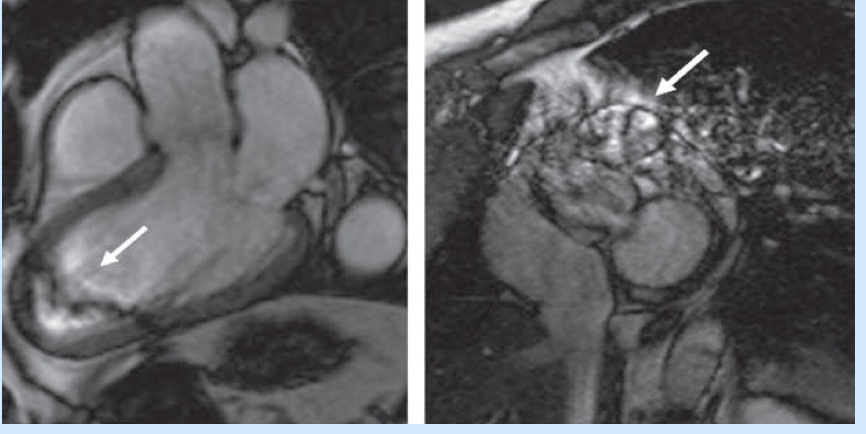

Common CMR artifacts